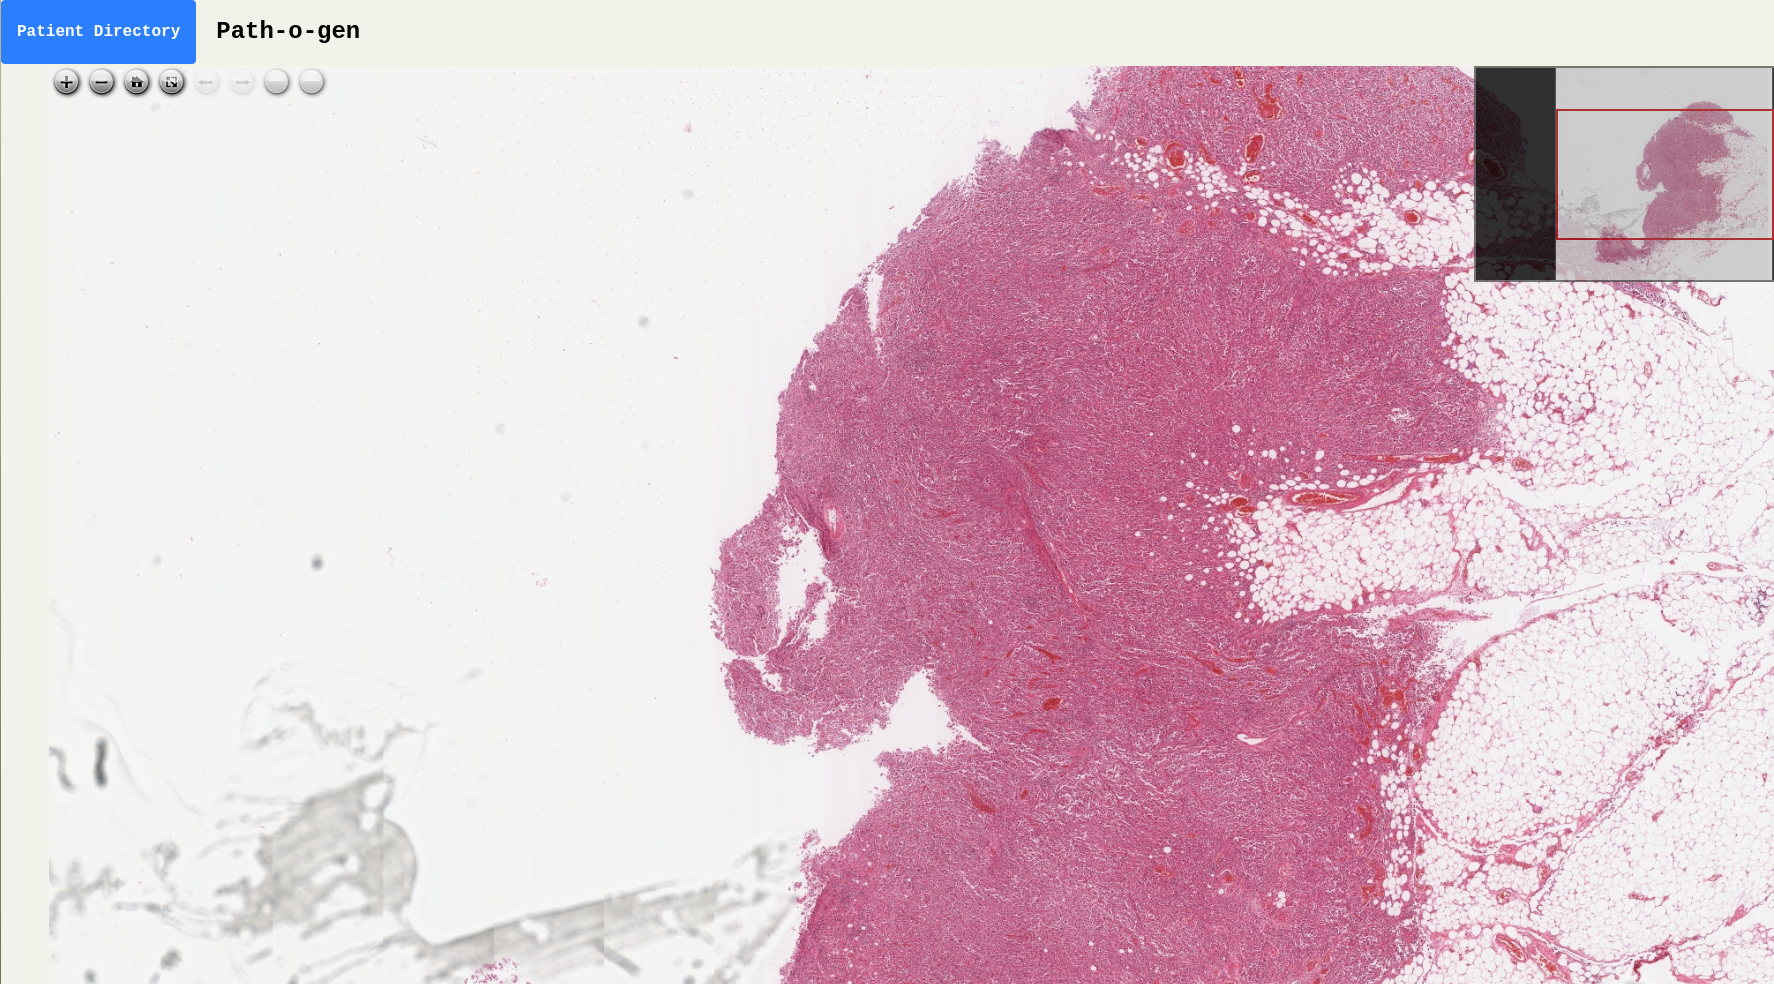

As such, there is a growing interest in "digital pathology" - in which slides are scanned using extremely high resolution cameras to match the optical resolution of professional microscopes. These images are often in the tens of thousands of pixels in each dimension and must be stored without lossy compression in order to preserve diagnostic detail (e.g. easily up to 20 GB). The high-resolution scanners are expensive but the approach is far more scalable since one scanner can be used to continuously scan slides and accessed by pathologists with access to computers everywhere. Furthermore, the digitisation of slides makes computational research far more amenable, which in the long term will increase the accuracy of diagnoses and improve patient outcomes.

Our platform is a website that allows digital pathologists to view high-resolution case imagery with the added feature of using a mask generating convolutional neural network to generate a "heat map" for areas of concern on the tissue samples. These are highlighted to the doctor, allowing them to choose to examine these critical areas first.

In order to test the platform, we have used sample slide images from the database hosted and maintained by the National Pathology Imaging Co-operative.